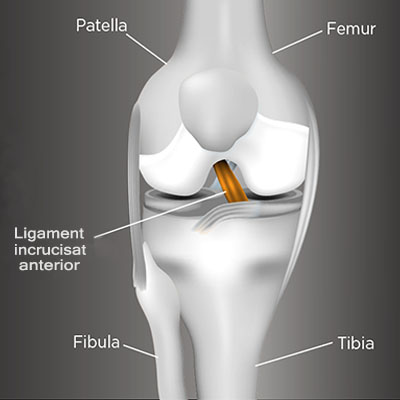

Genunchiul are o regiune anterioara si una posterioara. Articulaţia genunchiului este formată din 3 oase: femurul, tibia şi rotula (sau patela).

Rotula are rol protector asupra genunchiului şi acţionează ca o pârghie pentru muşchi. Femurul este legat de tibie prin 4 ligamente, intre care si ligamentul incrucisat anterior.